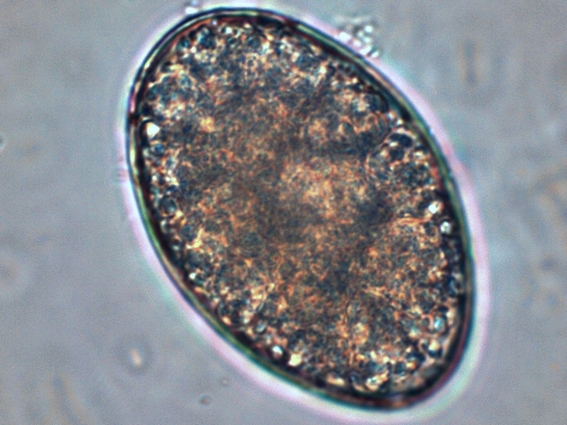

Яйца Широкого Лентеца Фото

Яйца Широкого Лентеца Фото 101 фото